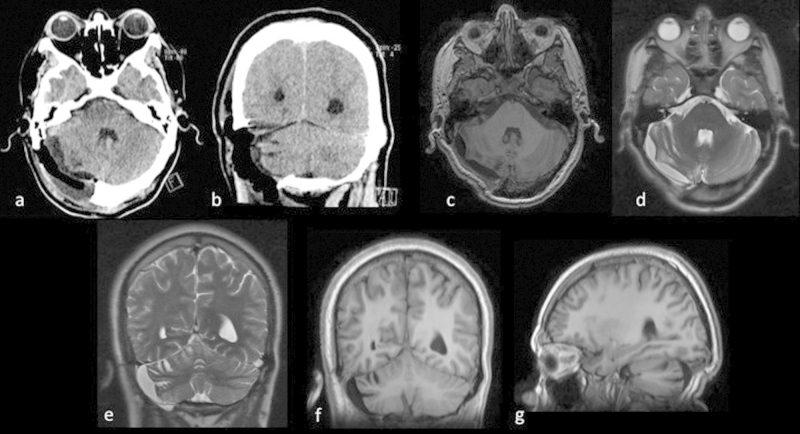

Fig. 1.

Tomography images (a–d) and MRI (e and f): where space occupying lesion is observed, extra-axial, right suboccipital, with significant erosion of the occipital squama (c, d), heterogeneous, predominantly hypo dense in tomography (a, b) and in the T1 weighted MRI sequence (e), hyper intense on T2-weighted sequence (h), which does not enhance with gadolinium administration (e, g) and restricts the diffusion sequence (f). Significant mass effect upon the cerebellar hemisphere and the right middle cerebellar peduncle is observed, in addition to compression of the fourth ventricle, without causing acute hydrocephaly.

Fig. 3.

Images of post-surgery studies tomography (a and b) and MRI (c–g), where we can observe the absence of lesion and how the structures compressed by it, return to their place.